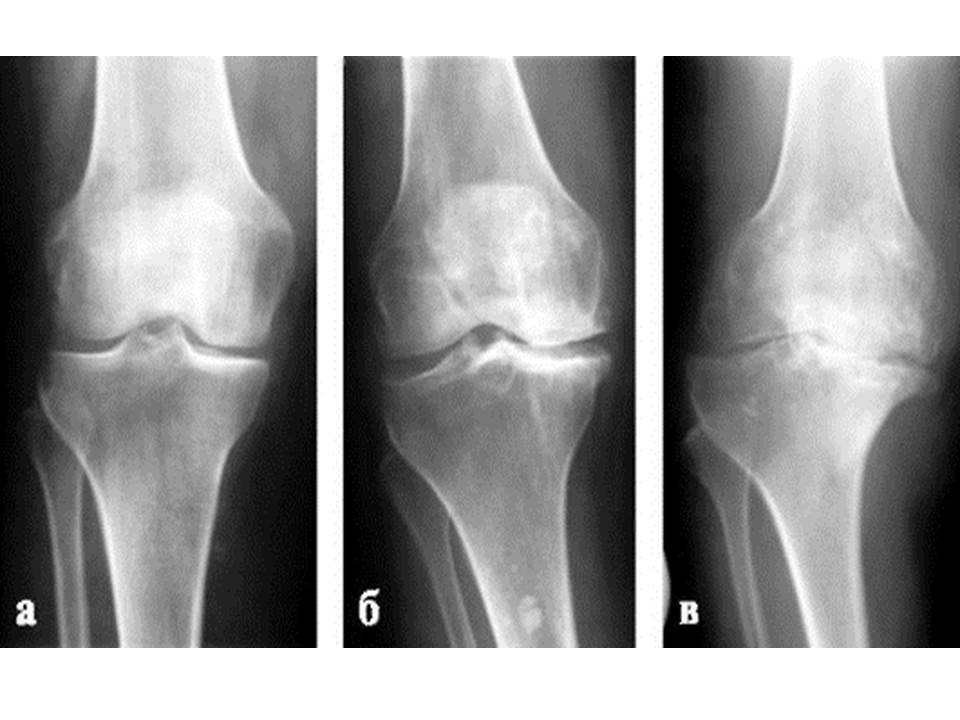

Полезно знать! Осторожно Артроз! Введение.